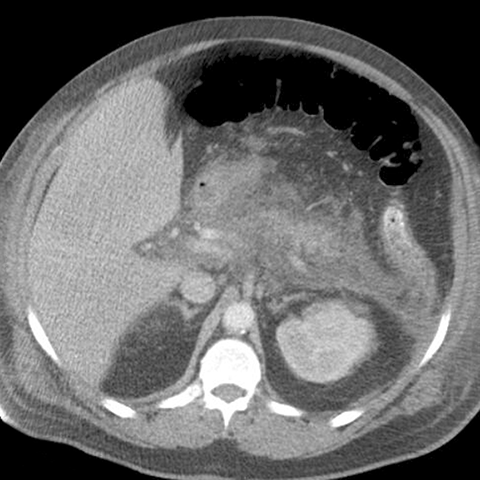

32-year-old man with severe epigastric pain after heavy partying [1 of 2]